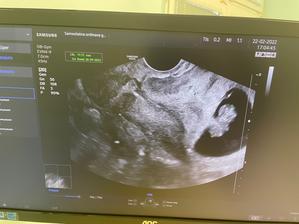

Tyden po kontrole 14.1.2022 jsem našla dvě carky na testu. Byl to docela šok, vzhledem ke štítné zlaze a 4,5 letech neúspěchů. Dvě carky stále sili, ale strach je veliký.